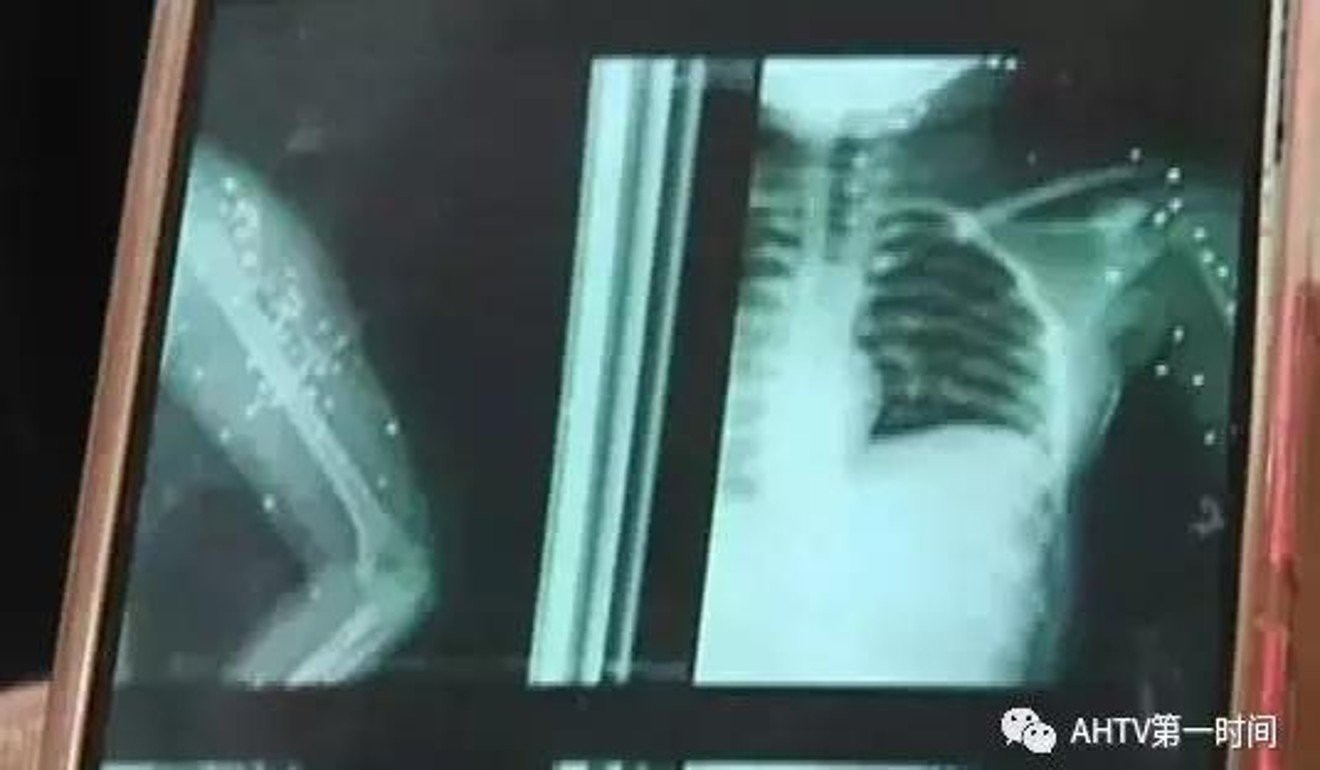

Sự việc đáng tiếc này xảy ra vào tháng 12 năm ngoái tại Phụ Dương, Trung Quốc. Theo tờ Anhui Business News đưa tin, khi đó, Zhang Shuting, 11 tuổi, đang đi ngang cửa hàng tạp hóa thì vô tình bị trúng liên tiếp hơn 100 phát súng từ một cậu bé 8 tuổi. Cậu bé này trước đó vừa nhặt được khẩu súng bắn chim dưới đất và tưởng nhầm là đồ chơi nên vô tư đùa nghịch và gây ra hậu quả nghiêm trọng.

Bị tấn công bất ngờ, Zhang không thể tránh né kịp thời. Ngay sau khi trúng đạn, cô bé đã cảm thấy chóng mặt và nhanh chóng được đưa đi bệnh viện cấp cứu. Tại đây, các bác sĩ xác định Zhang bị tổn thương nhiều khu vực trên cơ thể, trong đó có hệ thần kinh, và cần phải lập tức được phẫu thuật để lấy đạn ra khỏi người. Bệnh viện cũng không cam kết có thể lấy ra hết được toàn bộ đạn trên người cô bé không vì chúng nằm ở khắp nơi, sâu trong da thịt.

Sau khi phẫu thuật, Zhang đối mặt với nguy cơ bị liệt một phần cơ thể vì hơn 10 viên đạn vẫn còn nằm ở cổ và 9 viên khác rải rác khắp tay phải của em.